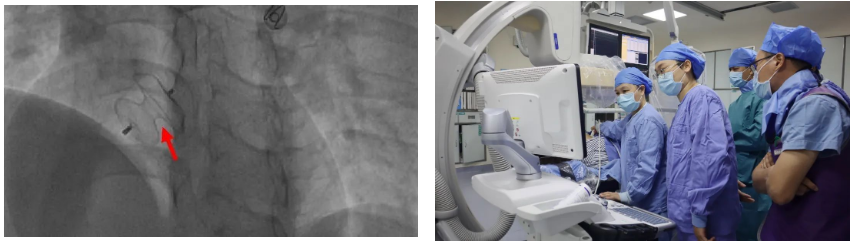

【首例】在中山一院龙明教授指导下,我院完成首例经皮房间隔缺损介入封堵术治疗先心病

心脏手术犹如“刀尖上起舞”,稍有不慎将造成严重后果,本着一切“以患者生命健康为中心”宗旨,在中山一院帮扶专家龙明教授的指导下,我院心内科、超声医学科、介入室等共同为患者制定了详细的手术方案——DSA下行房间隔缺损封堵术。

排除手术禁忌后,征得患者同意,手术由龙明教授、刘扬主任共同开展,在患者右侧股静脉穿刺点局麻后,送入导管行右心导管检查,准确测量肺动脉压、右房压、右室压、左房压,依据房缺大小选择封堵器,在DSA下封堵器被精准输送至房间隔缺损处一次性释放成功,术中超声医学科黄碧霞主任为患者行心脏彩超显示封堵器释放成型良好,无明显分流。牵拉实验提示封堵器固定牢固,且对二尖瓣、三尖瓣及上下腔静脉均无影响。整个手术过程严谨、配合有序,直至手术完成,用时还不到1小时。

该项新技术的突破,实现了我县县域内房间隔缺损封堵治疗的首例。标志着我院心血管内科在结构性心脏病的介入治疗上迈出了坚实的一步,同时为“大病不出县”奠定坚实基础。